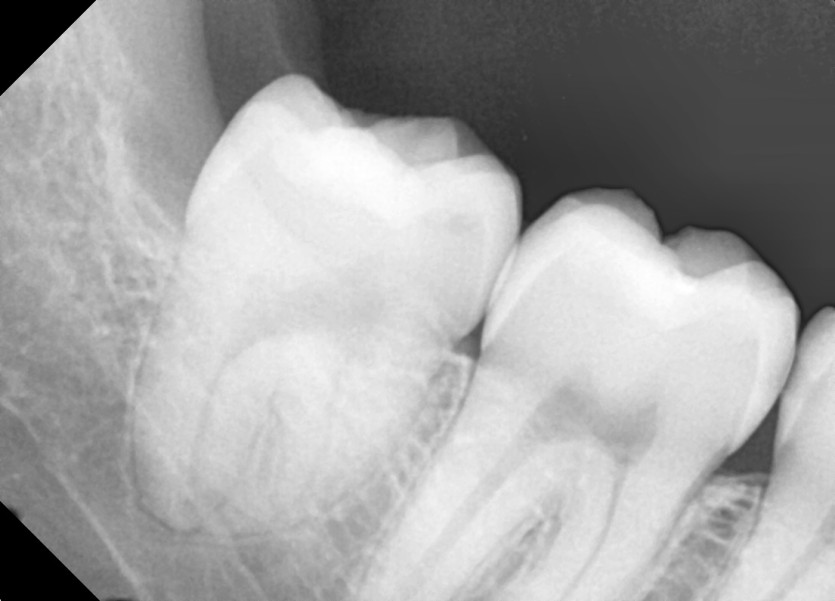

#18,48 사랑니 발치

구강외과 전문의가 당일발치했습니다.